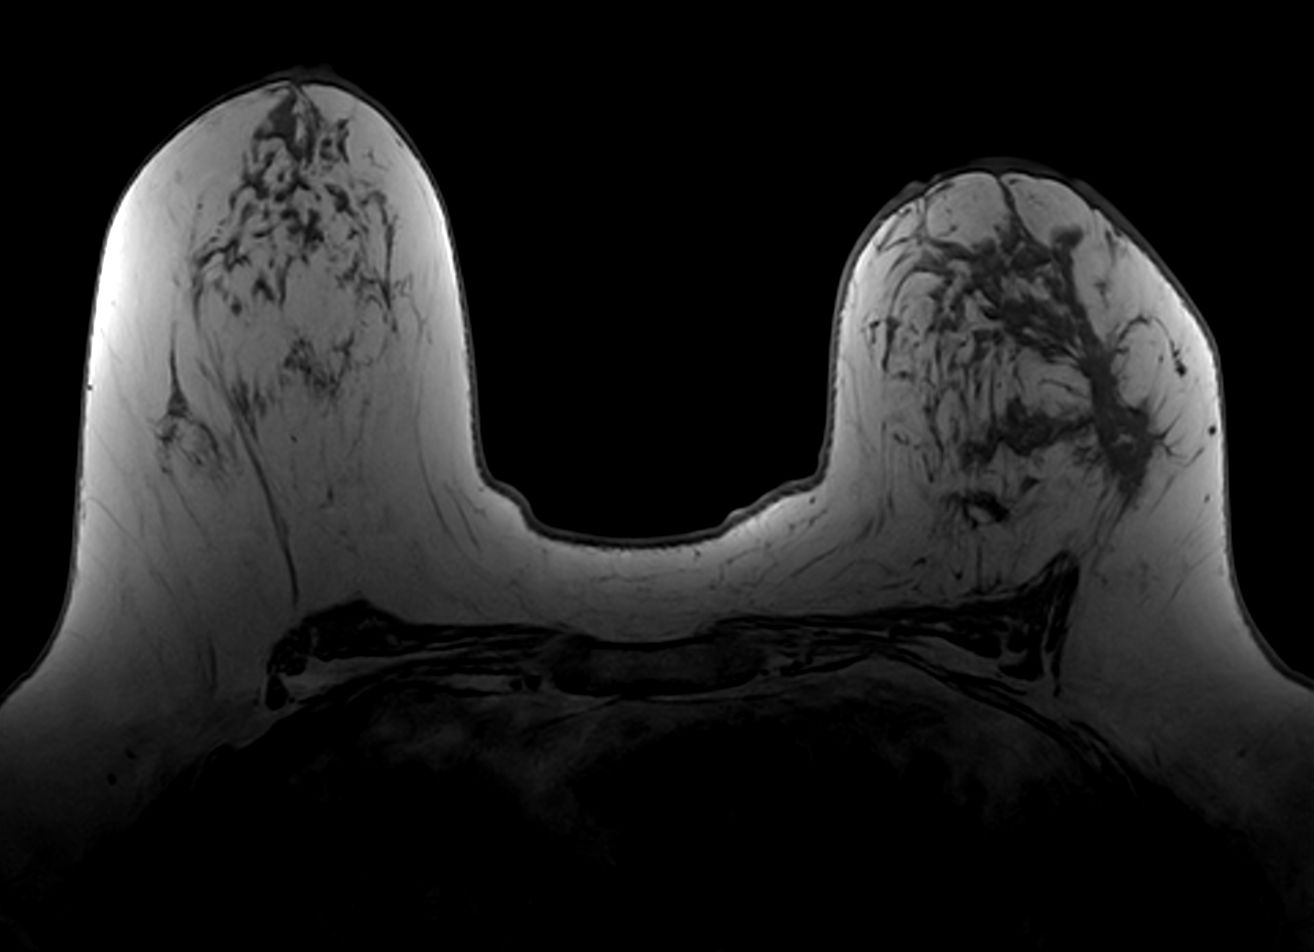

Axial T1w FFE mDIXON